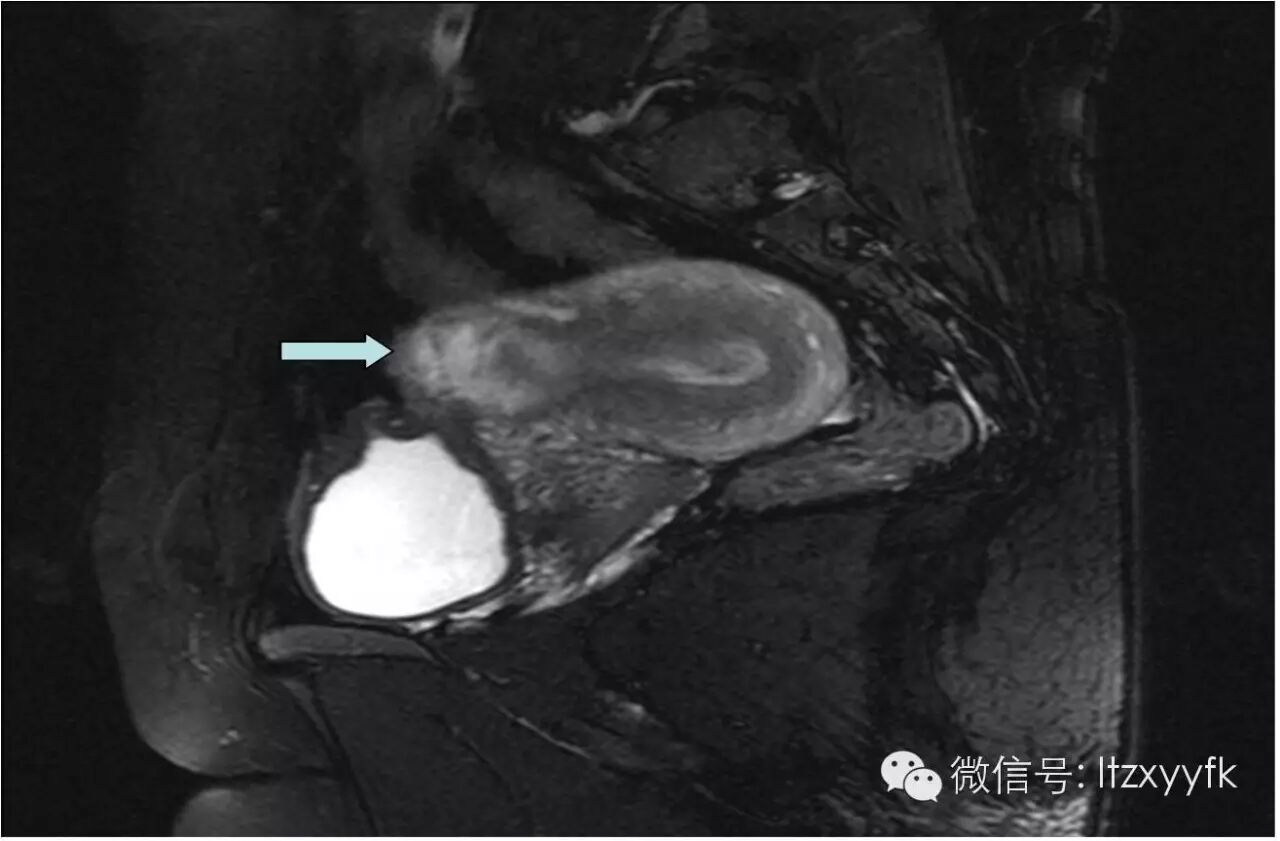

别急,有杀手锏,那就是影像学检查,比如B超、MR等。B超下可以看到向膀胱方向凸起的CSP二胎前,你需要了解的事儿–剖宫产瘢痕妊娠-怀孕期

,简单快捷,但是需要超声医生具一定的经验;

MR就更清楚了二胎前,你需要了解的事儿–剖宫产瘢痕妊娠-怀孕期

,甚至可以了解肌层植入的情况,然而就是太贵了;最后还有更直观的腹腔镜下观二胎前,你需要了解的事儿–剖宫产瘢痕妊娠-怀孕期